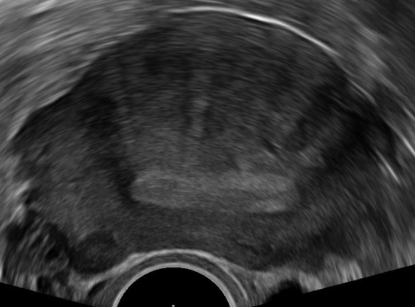

Transvaginal _____ is done to differentiate between the bicornuate uterus and a septate uterus if either is suspected on HSG